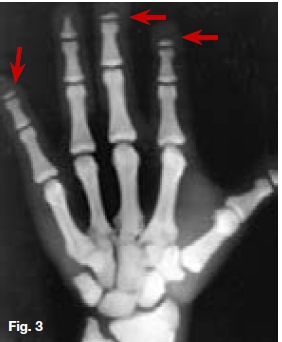

Below are cases of two very rare genetic disorders. Figures 1, 2 & 3 are of an inherited form of dwarfism associated with fragile bones, while Figures 4, 5, & 6 are cases of metabolic disturbances affecting the skull, jaws and teeth. Describe the important radiological features discernible and what are your diagnoses?

Postero-anterior skull (Fig. 1) and lateral skull radiographs (Fig. 2) showing open anterior fontanelle, dense bones and small maxillary sinuses. In addition, Figure 2 also demonstrates obtuse mandibular angles. The hand-wrist radiograph (Fig. 3) shows incomplete terminal phalanges (red arrows). A diagnosis of Pyknodysostosis was made which is a genetic lysosomal disease characterized by short stature, increased density of the bones, and brittle bones. Other features may include underdevelopment of the tips of the Angers with absent or small nails, an abnormal collarbone (clavicle), distinctive facial features including a large head with a small face and chin, underdeveloped facial bones, a high forehead, and dental abnormalities. These patients are predisposed to osteomyelitis. The diagnosis of Pyknodysostosis is based on physical features and X-ray findings. Figure 4 is a lateral skull radiograph of a patient presenting with bulging of the frontal region of the skull and showing attenuation of the outlines of the dental crypts which is suggestive of a child with vitamin D deficiency. This deficiency results in rickets in childhood and is one of the causes of osteomalacia in adults. Vitamin D acts to increase intestinal calcium uptake, bone calcium mobilization reabsorption.